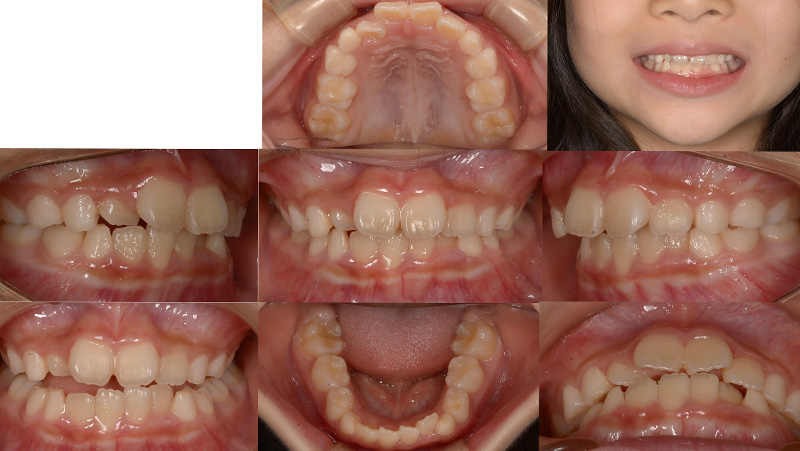

Case01インビザライン・ファーストによる矯正治療例

お子さんの前歯のガタガタが気になると来院されました。今の歯並びも気になるが、大人の歯に生え変わった後も綺麗な状態にしてあげたいという保護者のご希望があり、小児矯正から生え変わったあとの矯正までをしっかりとサポートする「通期矯正」を行いました。

初診 2021.7.31

矯正開始1か月 2021.9.18

矯正開始2か月 2021.10.30

ファイナル 2022.2.12

| 主訴 | 上下顎前歯のガタガタ |

|---|---|

| 診断 | ターミナルプレイン バーティカル 上下顎前歯叢生 |

| 矯正方法 | インビザラインファーストによるマウスピース矯正 |

| 矯正期間 | 6か月・8回 |

| 費用 | 490,000円(税別) |

| 調整料 | 月1回 5,000円(税別) |